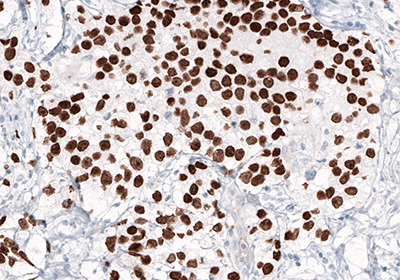

Figure 1A.

Figure 1 (A,B,C). NANOG protein normally is expressed during early embryonal development, and is absent in normal adult tissues. Overexpression of NANOG is observed in testicular embryonal carcinoma (A), shown by IHC staining (B) using monoclonal Anti-NANOG (AMAb91393). Anti-NANOG antibody AMAb91393 also shows nuclear positivity in NTERA-2 cells and band of expected size in the WB assay (C). NTERA-2 cells are pluripotent human embryonal carcinoma cell line, exhibiting biochemical and developmental properties similar to the cells of the early embryo.